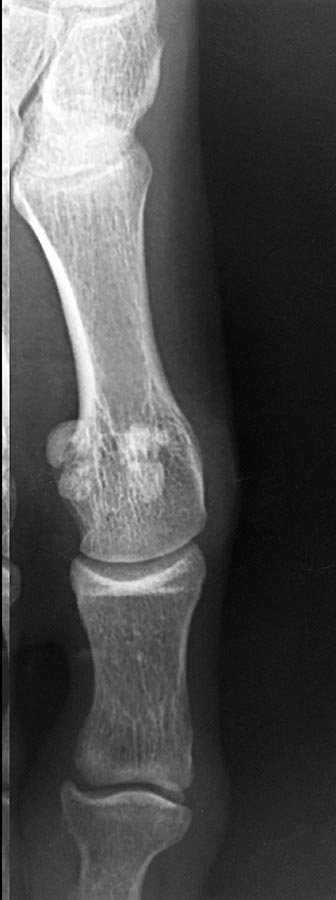

Снимки забыл приложить, извиняюсь.

По снимкам сложно определить, свежий ли это перелом или состоящая из двух частей сесамовидная кость. Поэтому смысл в МРТ есть. Еще на переднезадней рентгенограмме видны преобладание длины первой плюсневой кости и достаточно очевидные уже признаки артроза первого плюснефалангового сустава. Есть ли ограничение подвижности ПФС1 (hallux limitus)?